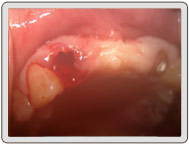

治療中

植入植體